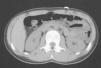

Aporta diferentes exploraciones complementarias: una ecografía abdominal, una ecografía ginecológica, una ecografía musculosquelética, una tomografía computarizada (TC) abdominal, una gammagrafia ósea planar, una resonancia magnética (RM) y un análisis sanguíneo. En la TC abdominal se observa una imagen patológica en el músculo rectus abdominis izquierdo, compatible con una cicatriz muscular (fig. 1). En la ecografía ginecológica se aprecia un quiste folicular en el ovario derecho, al que el ginecólogo no da importancia. En la ecografía musculotendinosa se ven 2 cicatrices fibrosas en el músculo rectus abdominis izquierdo a diferente nivel (fig. 2).

Figura 1